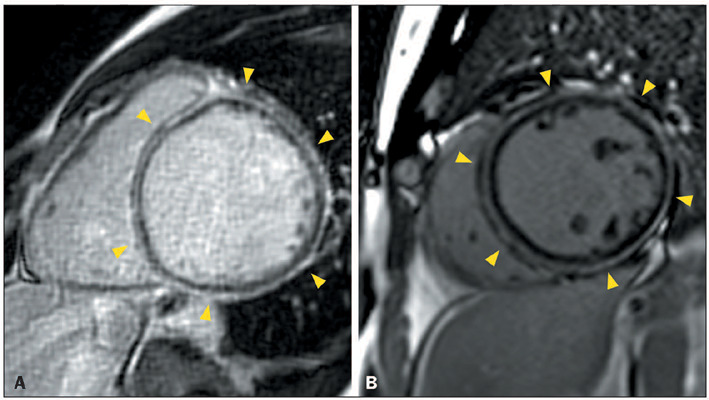

Advances in cardiac magnetic resonance have promoted tissue characterization with high spatial and contrast resolution, and late gadolinium enhancement (LGE) sequences have improved the detection of myocardial fibrosis. The distribution pattern of LGE facilitates differentiation between ischemic and nonischemic etiologies and aids in refining diagnoses within nonischemic cardiomyopathies, suggesting specific etiological factors. A distinctive nonischemic LGE pattern that has recently gained prominence is the ring-like pattern, defined as a subepicardial or mid-wall circumferential or semi-circumferential enhancement, which involves at least three contiguous segments within the same short-axis slice. Initially identified as a diagnostic marker for desmoplakin and filamin C-related cardiomyopathies, the pattern has been reported in nongenetic conditions; nevertheless, it remains an uncommon finding in these diseases. In this article, we aim to present the differential diagnoses of ring-like LGE and its mimics. The combination of epidemiological, clinical, electrocardiographic, and additional features enables a focused refinement of the differential diagnosis associated with ring-like LGE.

Abstract Image